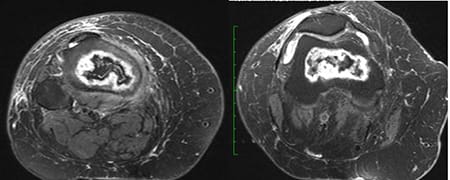

Paciente do sexo feminino, com 53 anos e quadro de dor crônica no joelho direito, principalmente na face anterior e medial. Ela refere piora da dor há uma semana, apresentando dificuldade na deambulação. Nega trauma e relata ter se submetido à cirurgia no tornozelo direito. Refere tratamento para asma brônquica com corticoide há anos.

Exames de imagem